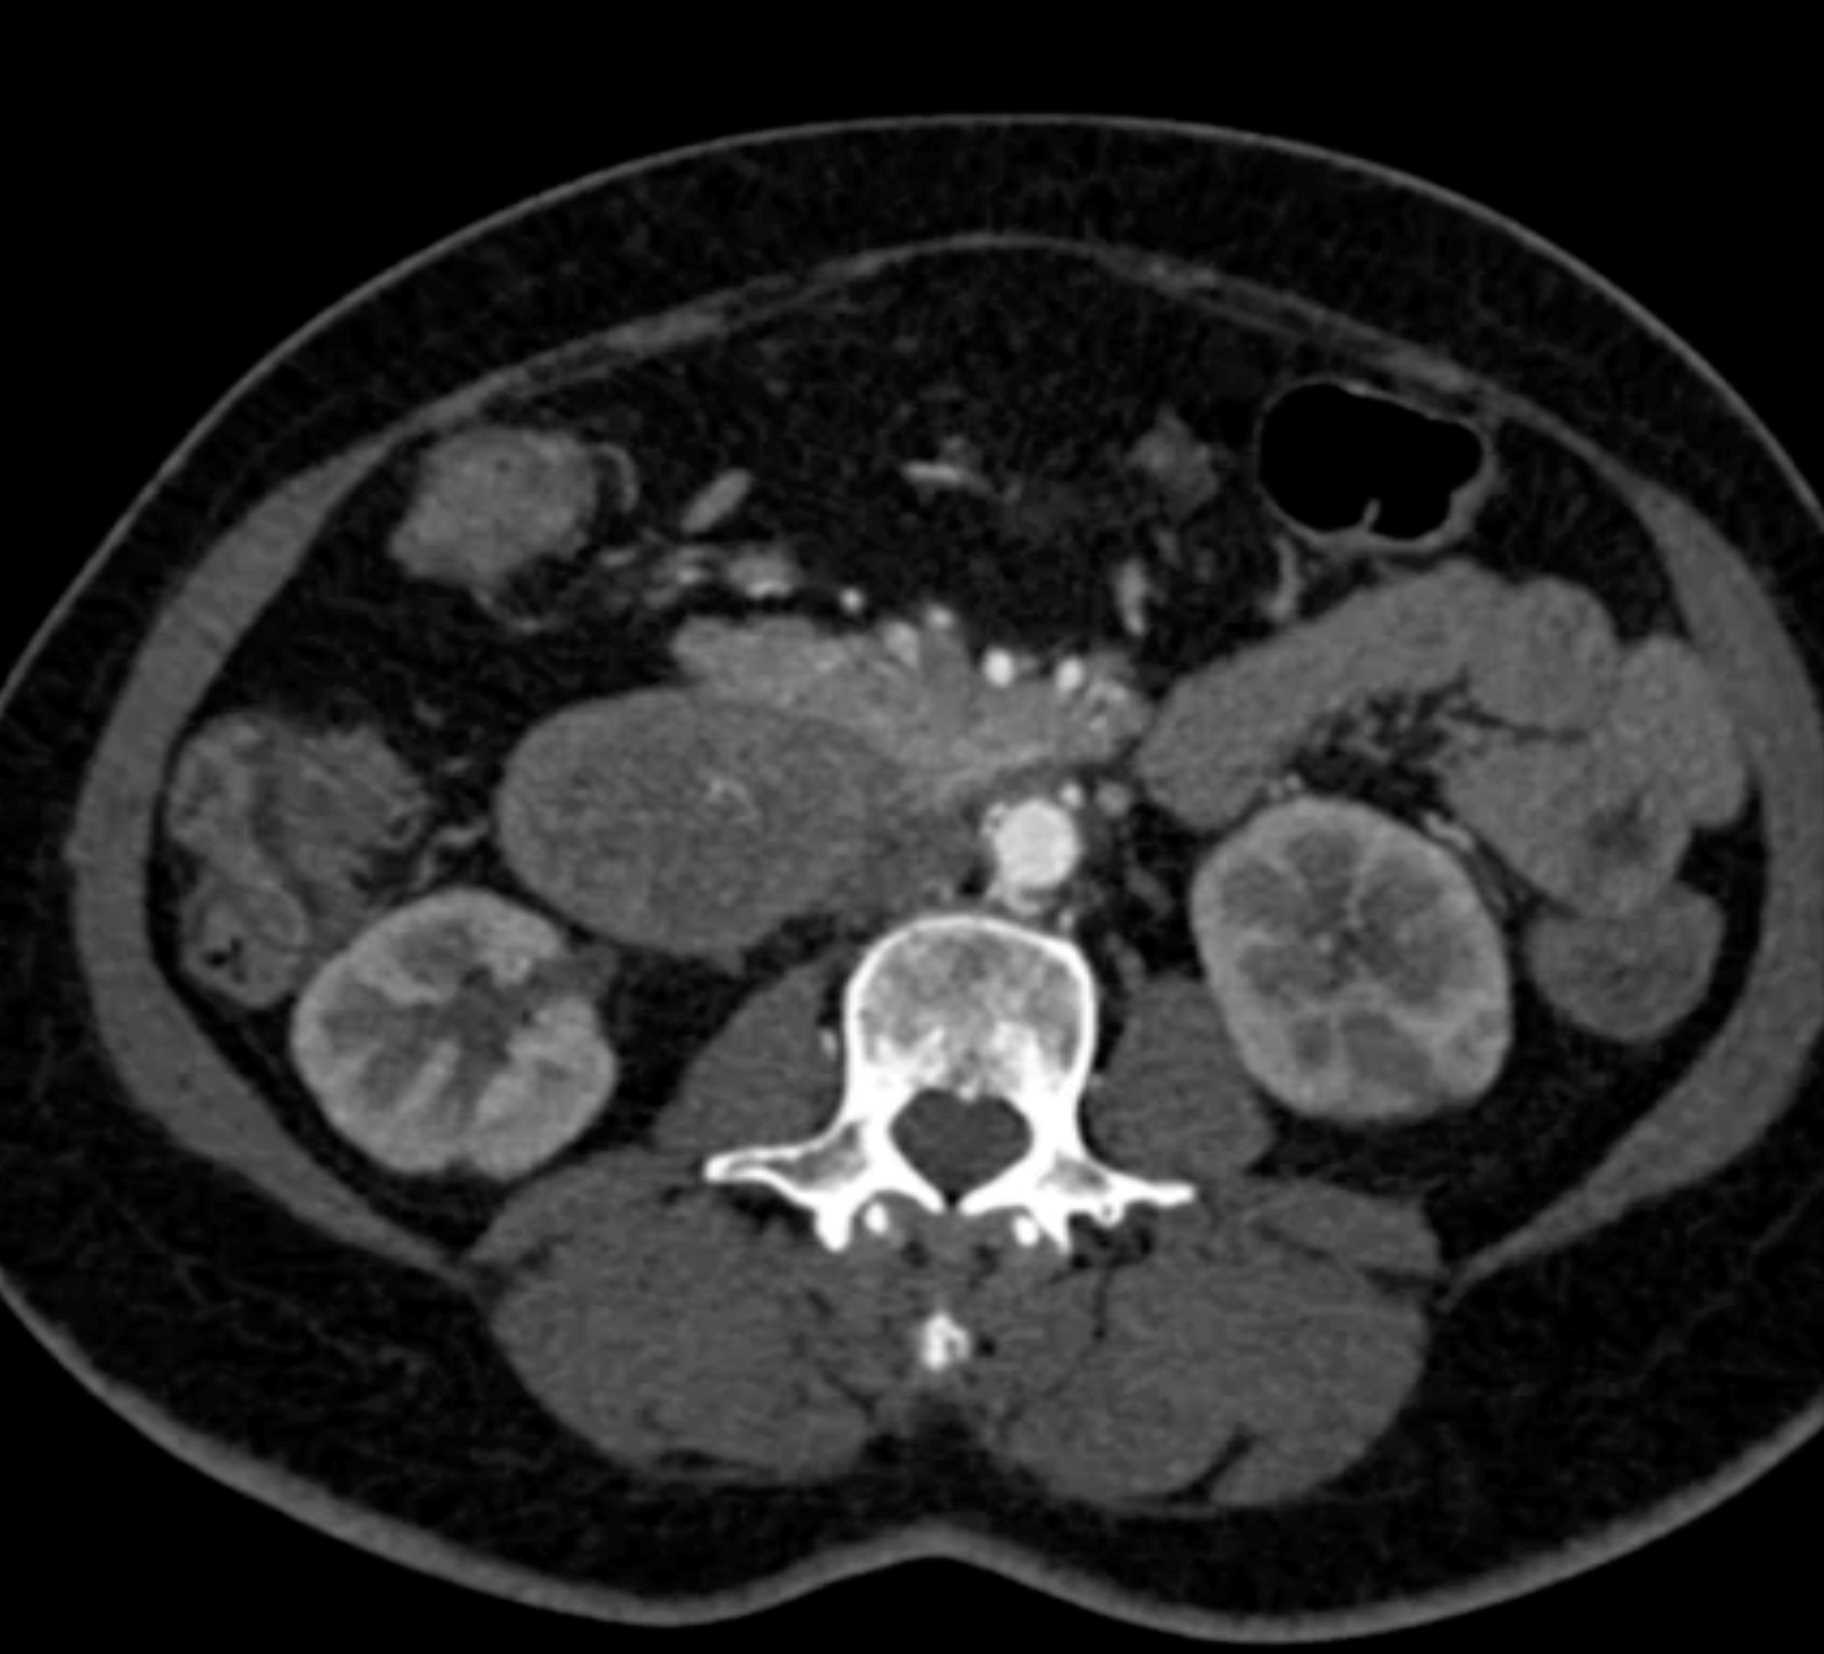

Lagre Gastric GIST Tumor